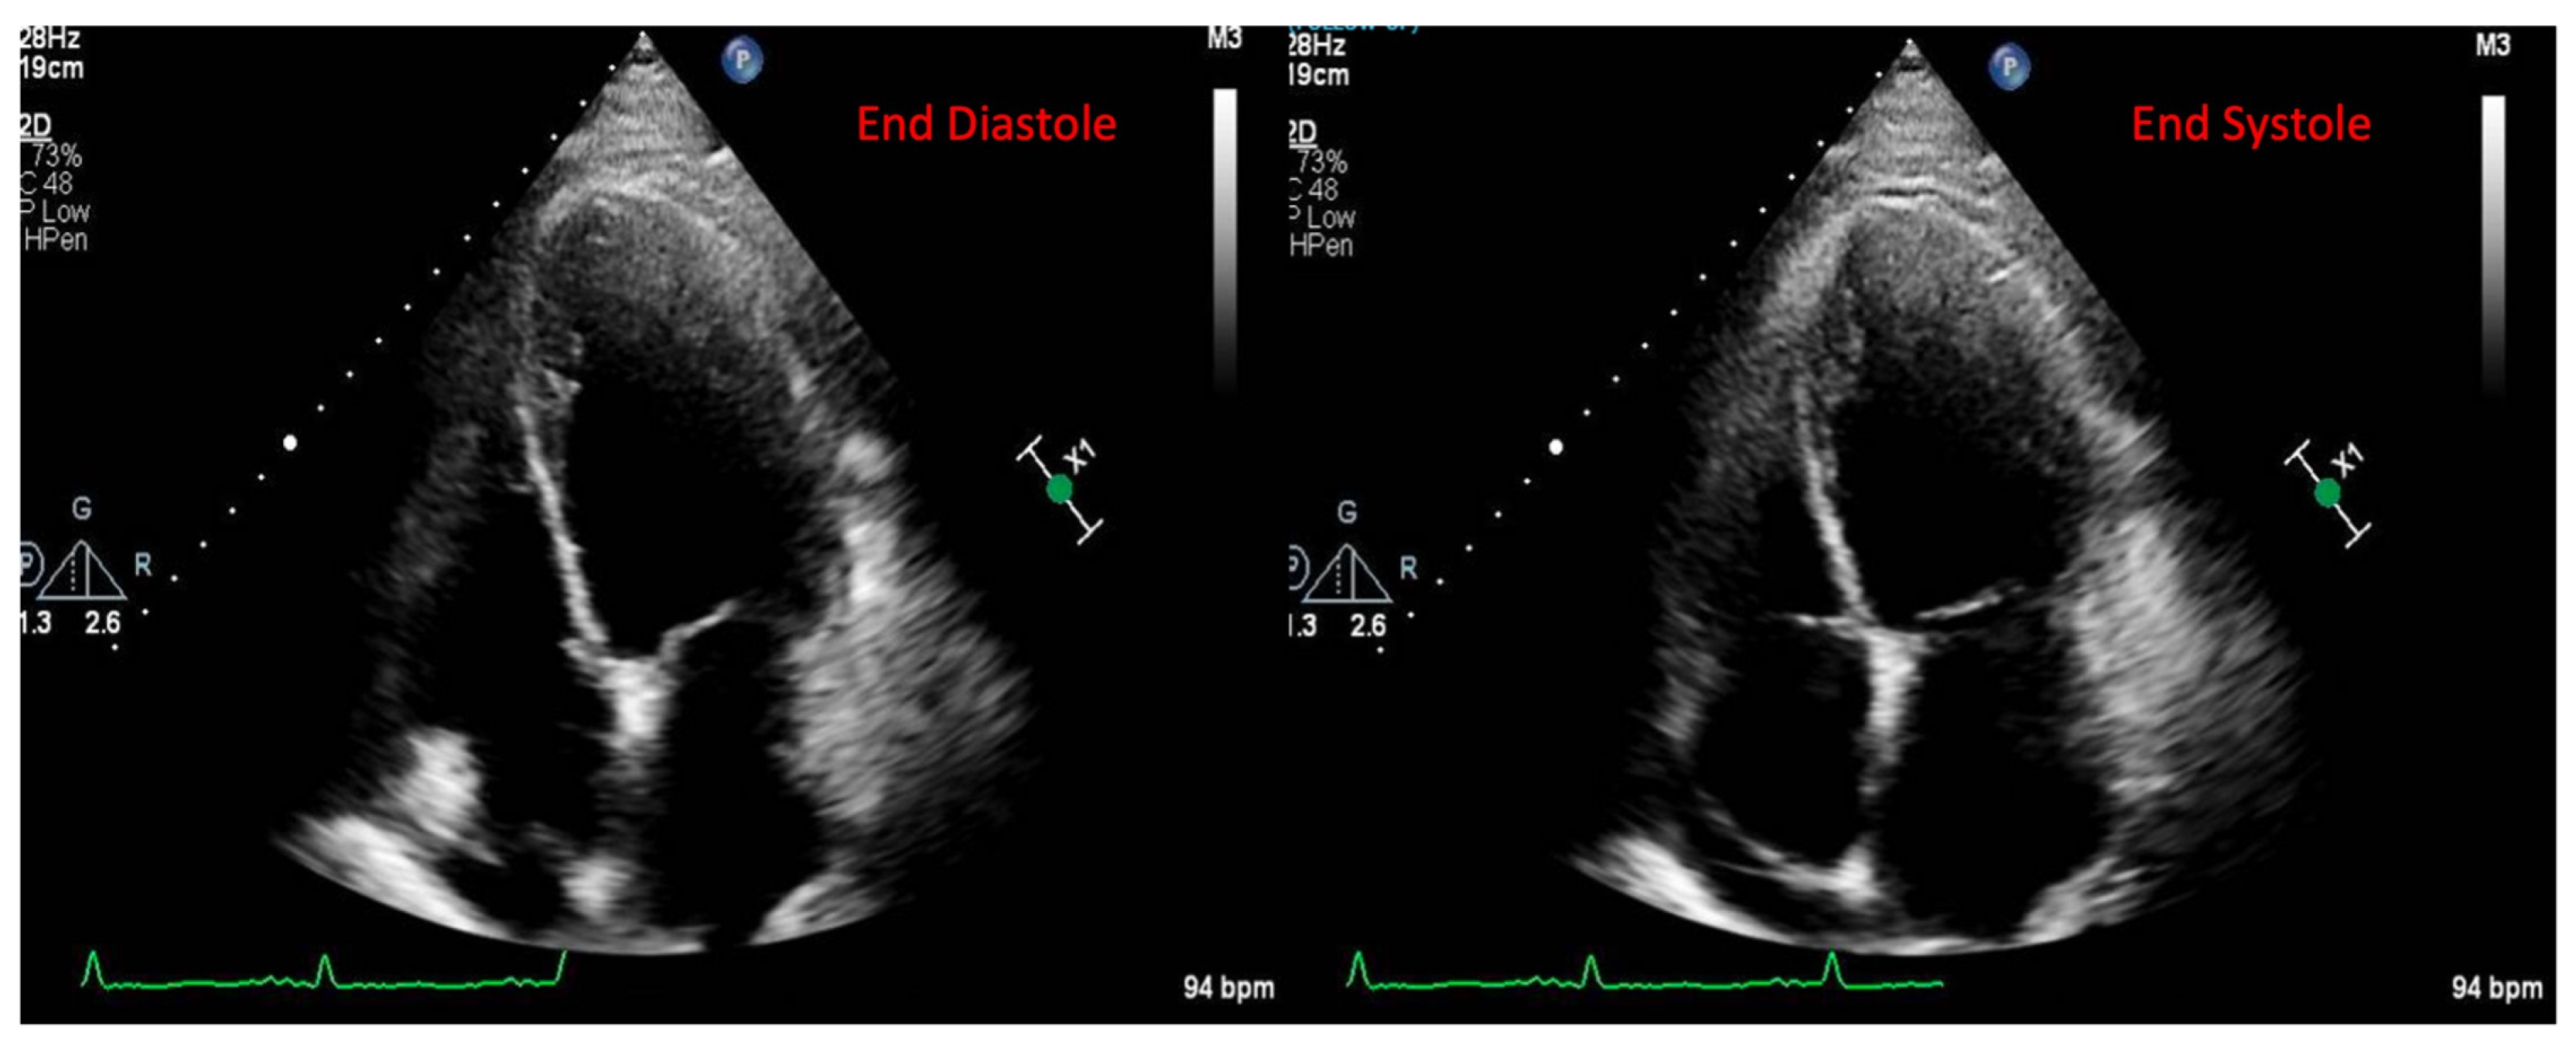

A 49-year-old male patient with a history of human immunodeficiency virus (HIV) was undergoing treatment for Kaposi sarcoma with cabozantinib and nivolumab (ICI) as the third line of treatment. Approximately 2 months after his last treatment, this patient presented to the emergency room with progressive shortness of breath over the last few weeks and was found to be in acute heart failure. An electrocardiogram showed sinus tachycardia with occasional premature ventricular complexes (Figure 2). The troponin I level peaked at 0.62 ng/mL (normal value < 0.03 ng/mL) and the B natriuretic peptide level was 1023 pg/mL (normal value < 100 pg/mL). The baseline echocardiogram prior to treatment initiation showed normal biventricular function, but his echocardiogram at presentation showed severely reduced left ventricular systolic function with an ejection fraction of 30% and a small pericardial effusion (Figure 3). Left heart catheterization demonstrated normal coronary arteries. Right heart catheterization demonstrated minimally elevated filling pressures and borderline cardiac output/index. An endomyocardial biopsy was taken, with pathology showing mild interstitial fibrosis, but no evidence of active myocarditis. Cardiac MRI showed linear mid myocardial LGE in the interventricular septum (Figure 4A) that corresponded with the areas of myocardial edema seen on the T2-weighted images (Figure 4B). There was also elevated native T1 map at 1470 ms (normal 1000 +/− 50 ms at 1.5T) (Figure 4C) along with elevated T2 mapping at 70 ms (myocardial edema suggested if T2 > 55–60 ms) (Figure 4D), and a small pericardial effusion. ECV was unable to be calculated due to an artifact on postcontrast T1 images. This case met the ICOS diagnostic criteria (Table 2, cTn elevation + diagnostic CMR (major criteria)). The patient was started on a pulse dose of corticosteroids for the treatment of presumed myocarditis with significant improvement in symptoms and was discharged home with a stable dose of steroids, as well as goal directed medical therapy for heart failure (beta blockers, ARNI, and SGLT2i). Nivolumab was discontinued. The patient was followed-up in the cardio-oncology clinic and, due to the resolution of symptoms, his steroid treatment was tapered over the next few weeks. During his follow-ups, he showed a complete resolution of clinical symptoms and was able to recover a good exercise tolerance, but unfortunately a repeat echocardiogram at 9 months after the initial presentation showed a persistently reduced ejection fraction.

Figure 3. Echocardiogram images from the clinical patient. Transthoracic echocardiogram apical 4-chamber images (shown at end diastole and end systole). Severely decreased left ventricular ejection (30%). Mild right ventricular dysfunction. Small pericardial effusion.